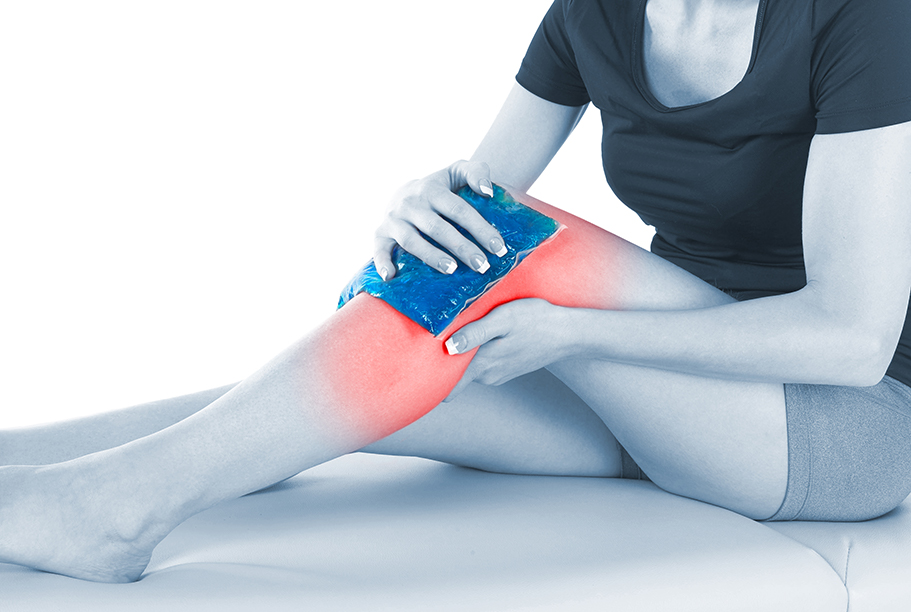

Ice (gheata). Gheata aplicata pe zona afectata combate durerea pe termen scurt si previne sau reduce considerabil edemul local, inflamatia prin reducerea fluxului sanguin local. Totusi, trebuie retinut ca nu se lasa mai mult de 20 minute o data gheata pe zona afectata existand riscul lezarii tegumentului la expuneri mai lungi. Cea mai buna metoda este reprezentata de aplicarea compreselor reci timp de 15 minute, pauza 20 minute de 4 -8 ori pe zi. Pentru zonele cu tesut muscular si adipos redus ca degetele, aplicatiile cu gheata se limiteaza la 10 minute o data.